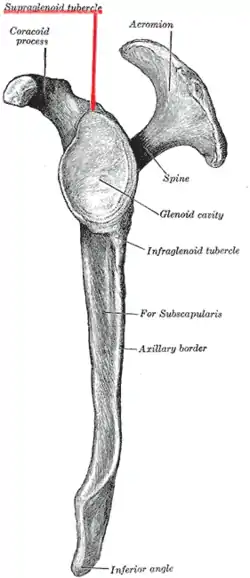

| Supraglenoid tubercle | |

Left scapula. Lateral view. Supraglenoid tubercle labeled in red. | |

Bones of left shoulder. Supraglenoid tubercle shown in red. | |

The supraglenoid tubercle is a region of the scapula from which the long head of the biceps brachii muscle originates.[1][2] It is a small, rough projection superior to the glenoid cavity near the base of the coracoid process. The term supraglenoid is from the Latin supra, meaning above, and glenoid, meaning socket or cavity.[3]

Position of supraglenoid tubercle (shown in red). left scapula.

Position of supraglenoid tubercle (shown in red). left scapula. Still image. Left scapula, lateral view.